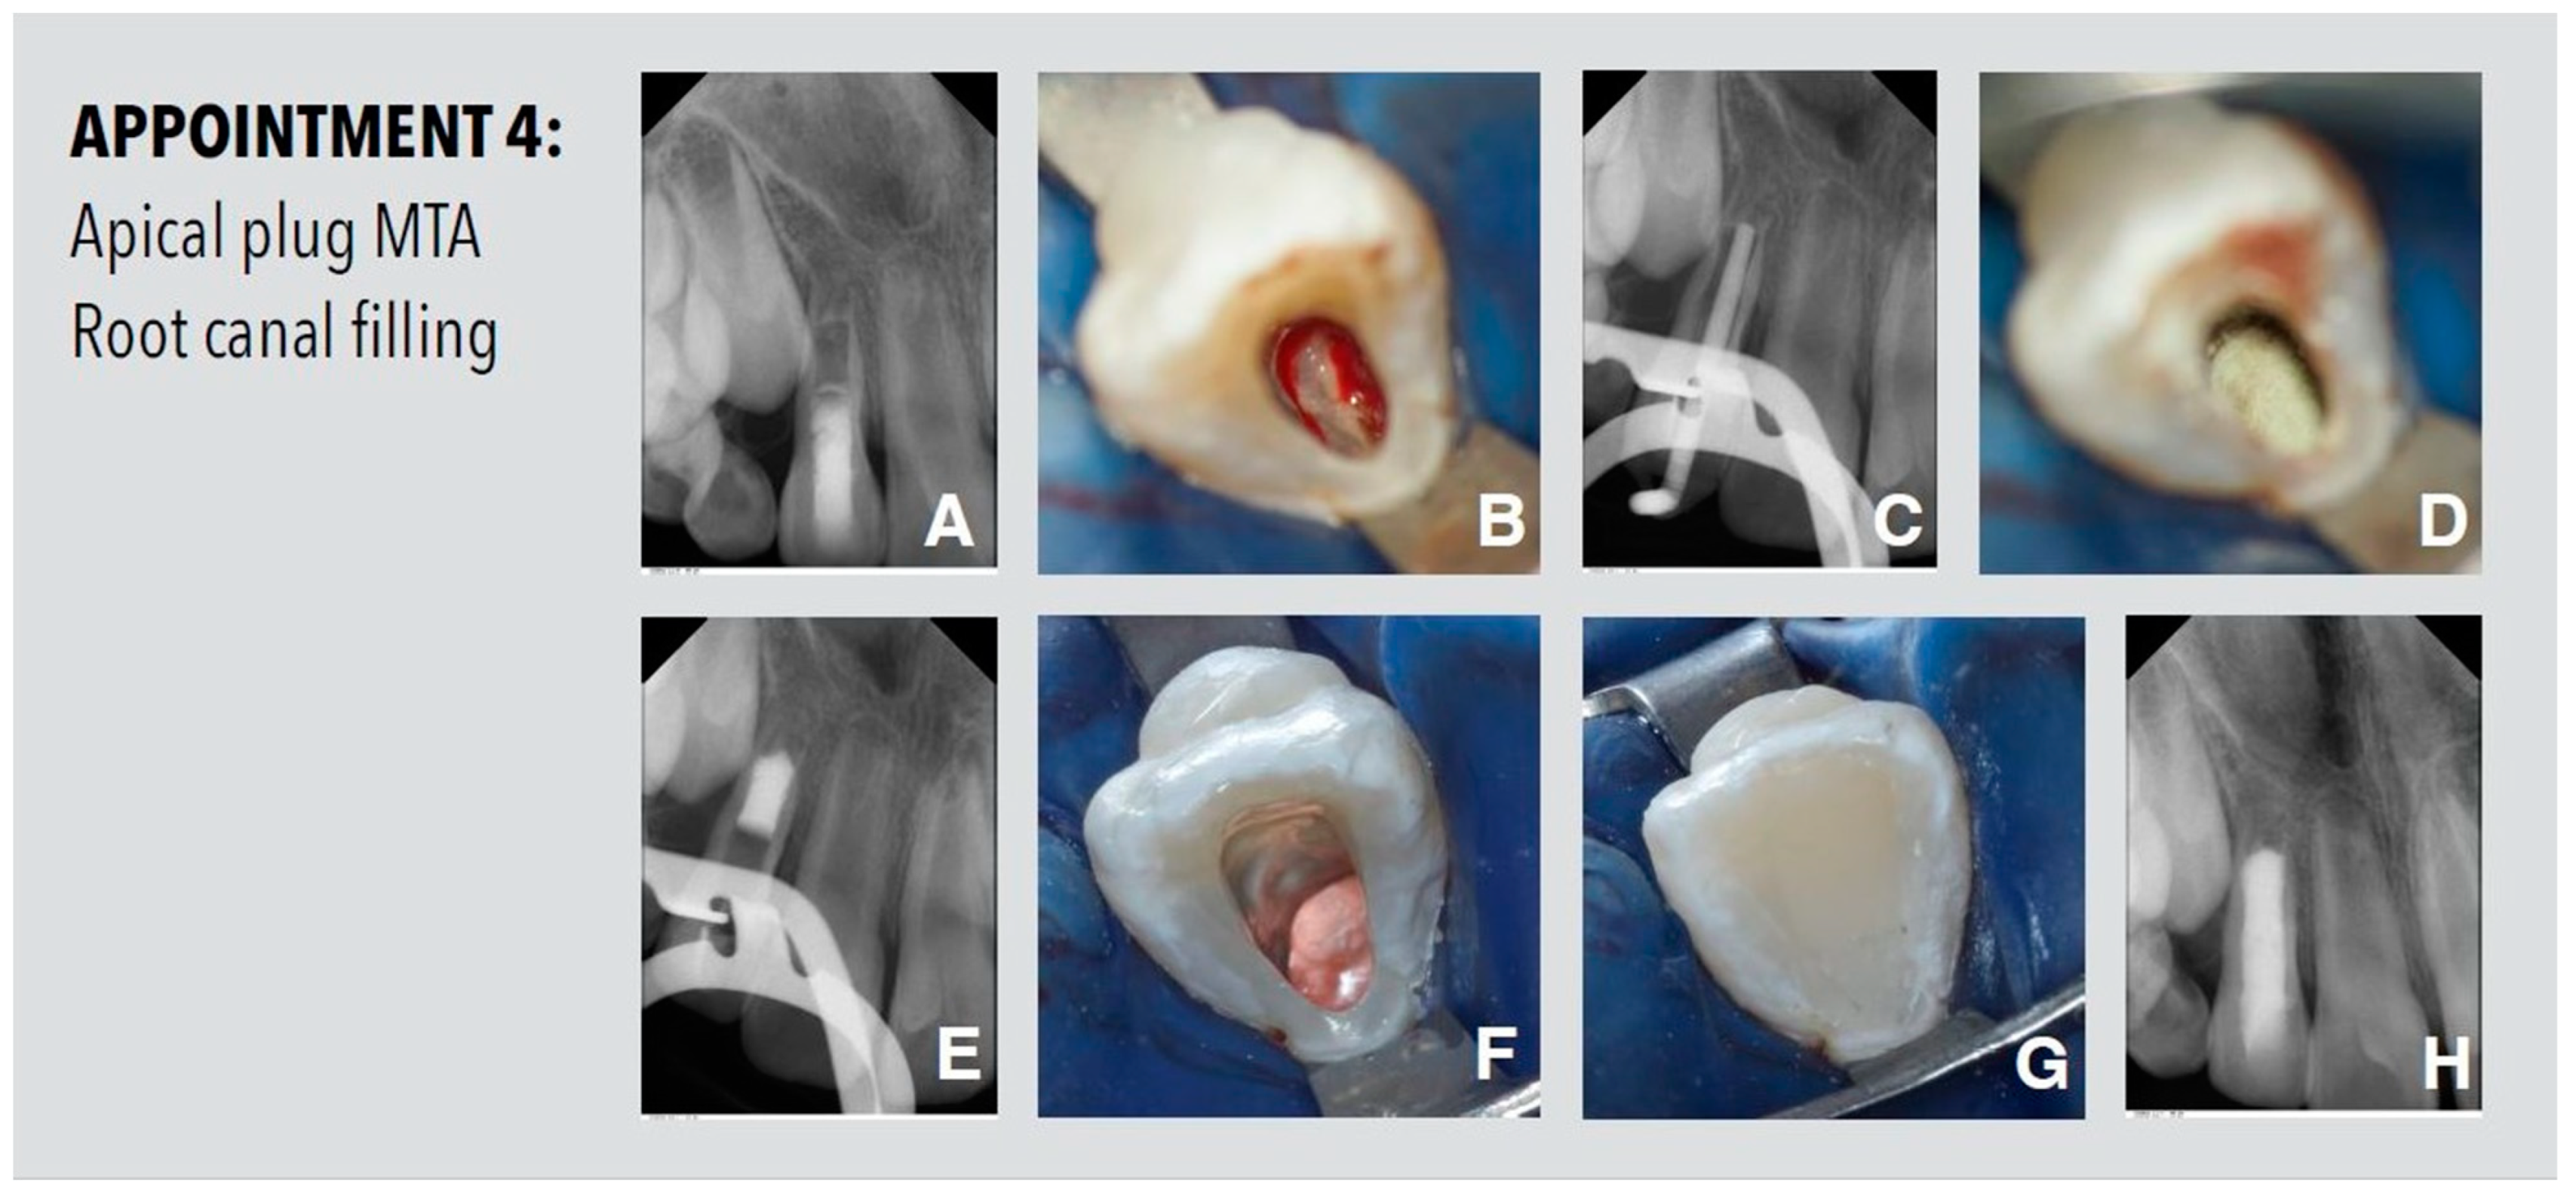

2.4. Appointment 4